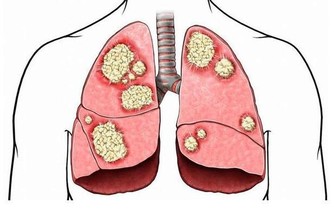

據美國紐約一家專門從事癌癥研究的權威機構透露,中國和日本婦女乳腺癌的發病率比西方低得多,這是為什麼呢?

科學家在比較了世界各國的三餐食譜後得出結論:是由於中國和日本婦女多吃大白菜的緣故。

調查資料表明,每10萬名婦女中,每年乳腺癌的發病率為:中國9人,日本21人,北歐84人,美國91人。

大白菜何來如此神功?

實驗證明,大白菜所含有的許多物質、具有防癌抗癌的作用,因此在美國國立癌癥研究所、發表的防癌食品排行榜中、將白菜排在僅次於大蒜的後面,名列第二。。

其次,大白菜含有一種叫做吲哚-3-甲醇的化合物,其含量約佔大白菜重量的0.01%,它能促進人體產生一種重要的酶,這種酶能夠有效抑製癌細胞的生長和分裂。

據測算,每天吃1磅大白菜,或白菜榨汁,每天飯後服200-300克,就能吸收到500毫克這種化合物,達到預防癌癥的目的。